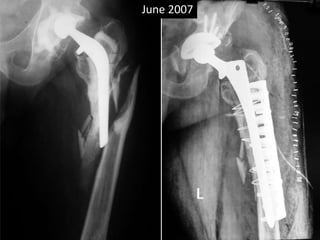

• 36 yrs Male

• Bilateral AVN hips

• AMP done 1988 rt side at the age of 36 yrs

• THR cemented done on left 1990 at the age of 38.

• Revision THR for shattered femur 2007

• Sciatic palsy

• Removal of Memmen plate and wires April 2009.

• Removal of THR Sept 2009.

• Metal fatigue 2012

• Last follow up Nov 2014.

Case Eighth

• Acetabular poly wear 2007.

• Sustained periprosthetic fracture with

shattered femur.

• Non cemented “Solution Hip” with Mammam

plate and circlage wires + bone grafting of

acetabulum.

• Sciatic nerve palsy.

• Persistent pain in hip

• Plate and wires removed in April 2009

• Pain in knee and hip persisting

• Solution hip system removed for suspected

low grade infection Sept. 2009.

• Serial x-rays showing broken amp in Jan 2012.

• Last follow up 2014.

• Sciatic nerve has partially improved.

June 2007